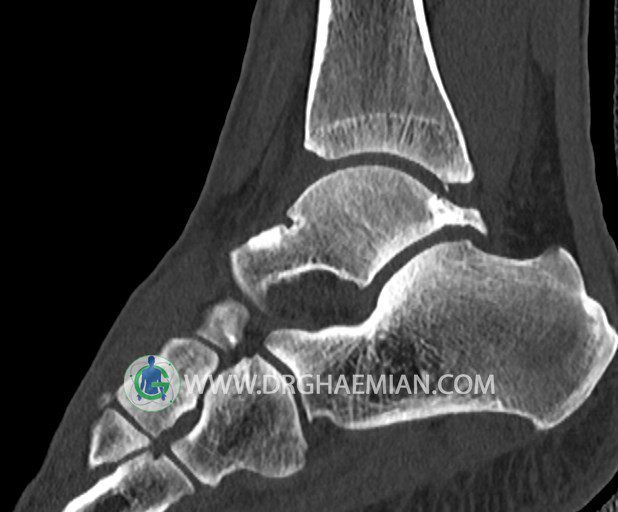

سی تی اسکن پا تصاویری عرضی از پا ایجاد می کند. این روش تصویربرداری از اشعه ایکس برای ایجاد تصاویر ایجاد می شود. در این کیس هيپرپلازي مچ پا، تورم نسج نرم و استئوفیت در مچ پا بیمار مشاهده می شود.

سي تي اسکن مچ پاي راست (مولتي ديدکتور 16 با مقاطع ظريف و بازسازي هاي ساژيتال و کرونال و 3D):

– تورم نسج نرمي در اطراف قوزک خارجي پاي راست

– Cortical Fx در قسمت خلفي اپيفيز ديستال تيبيا و

– هيپرپلازي lateral tubercle در تالوس ( stieda process ) همراه با اوستئوفيت در لبه

مديال تيبيا و تالوس